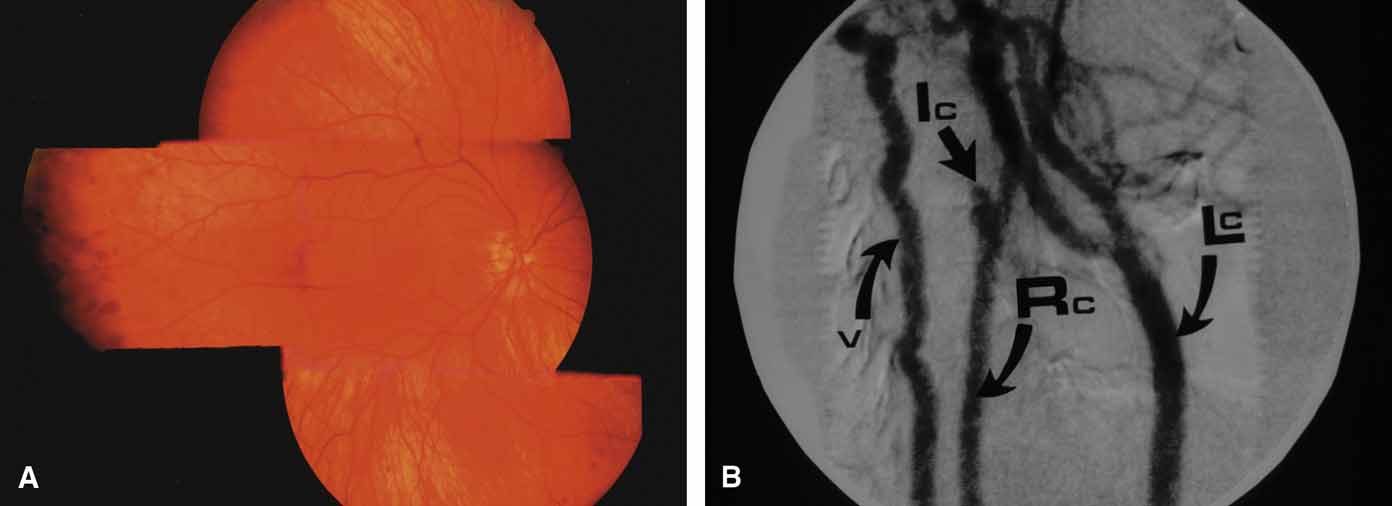

RAISED EPISCLERAL VENOUS PRESSURE

A review of the aqueous blood microcirculation of the eye (Fig. 10) explains how raised venous pressure can affect both retinal vessels and intraocular pressure. From Schlemm's canal, aqueous traverses the intrascleral emissary channels (aqueous veins of Ascher) to the episcleral plexus and then the long ciliary venous vessels. The long ciliary veins, as well as the vortex veins, empty into the ophthalmic vein before entering the cavernous sinus. Increases in episcleral venous backpressure theoretically contribute to a 1:1 mm Hg rise of measured intraocular pressure. The clinical result of an acute rise in external venous pressure may include choroidal effusion, elevated intraocular pressure with blood in Schlemm's canal (Fig. 11), and retinal vein obstruction with intraretinal hemorrhages in a central vein obstruction pattern with or without prominent swelling of the optic nerve. Chronic elevations of venous pressure may permanently damage trabecular meshwork, impairing outflow facility, and result in a chronic open-angle glaucoma.